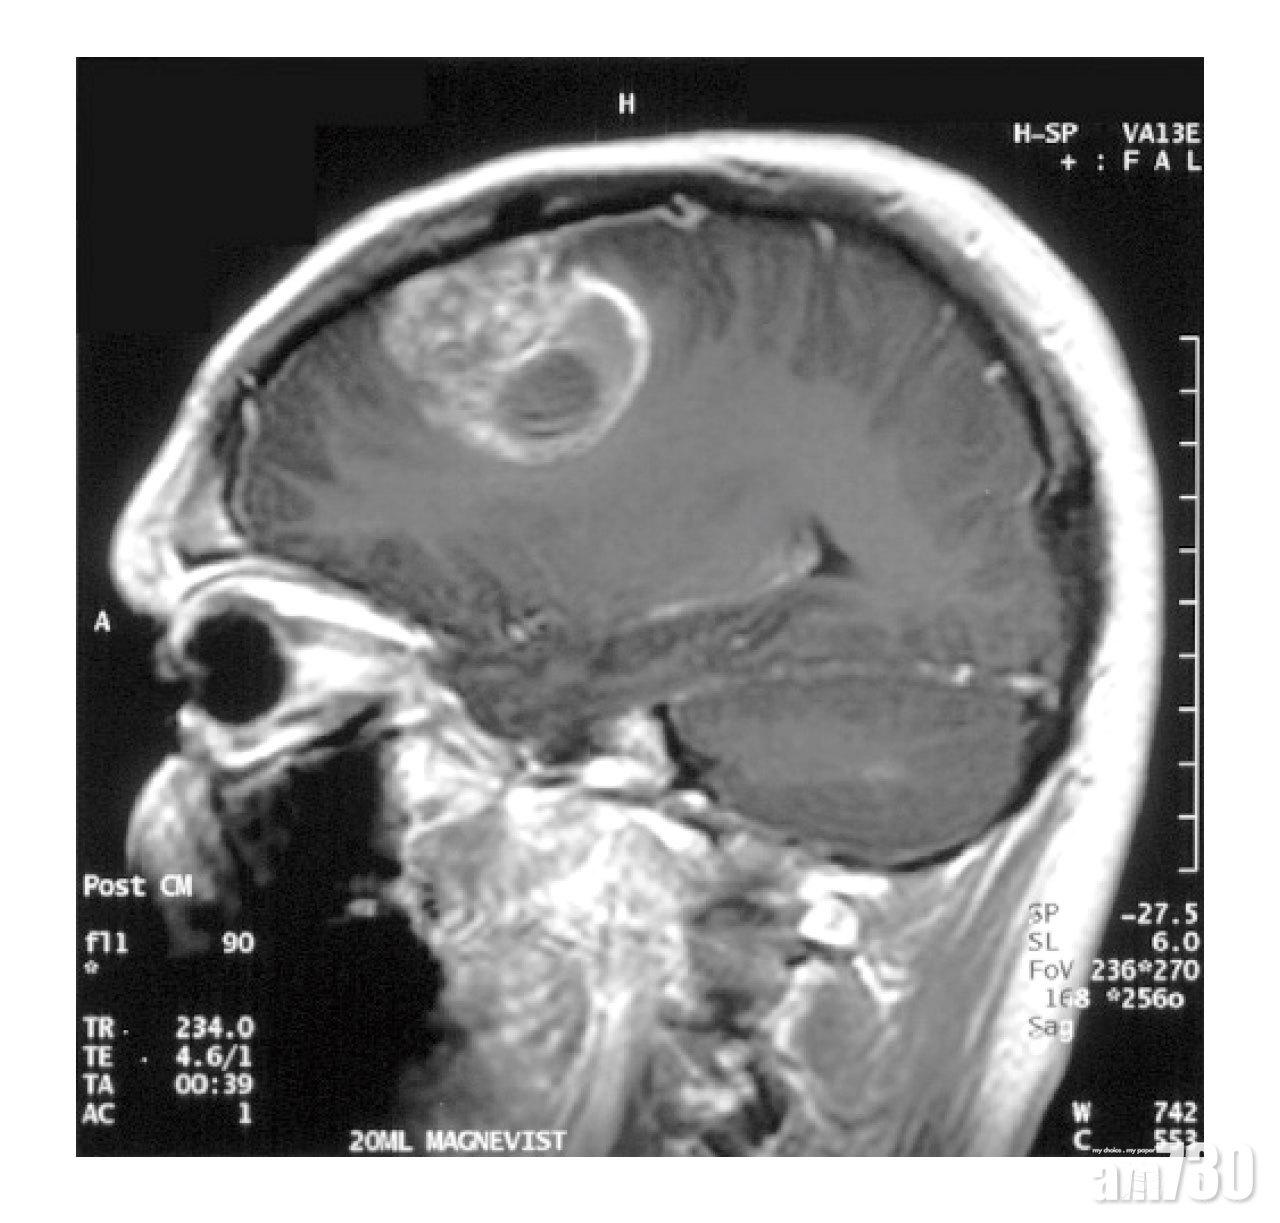

「今年的父親節,也許不能和女兒一起慶祝了。」現年48歲的Denis去年不幸確診膠質母細胞瘤(GBM),正在香港接受治療,因疫情爆發後有隔離規定,可能無法與居住在內地的愛女共度父親節。

臨床腫瘤科醫生吳雲英表示,腦腫瘤在香港並不常見,每年新症約200宗,而GBM是其中一種最具侵襲性的惡性腦腫瘤,即使接受治療,病人平均存活期亦僅為一年。「腦腫瘤成因不明,初期病徵亦不明顯,例如頭痛、頭暈、言語不清、記憶力和平衡力變差等,很容易令人忽略。」

Denis有一日工作時突然口齒不清,嘴巴也歪了,求醫後被診斷為中風,醫生決定動手術清除他腦中「血塊」。誰想到Denis顱內的「血塊」原來是腫瘤,而且是第四期GBM。驟然驚聞噩耗,所有家人都憂心忡忡,他反而是最冷靜的一位。「太太最初難以接受,很怕才7歲的女兒突然之間失去父親,一想起就哭。我就覺得有病就想辦法醫,家人的支持可以說是我對抗癌魔的一大動力。」Denis了解到GBM治愈率低、復發率高,但只要有一絲希望,任何治療他都願意嘗試。

吳雲英解釋,「惡性腦腫瘤生長快、復發率高,以GBM為例,以往接受治療後存活時間超過5年的病人只有5%。醫生會按病人的身體狀況、腦腫瘤範圍與位置等制訂最合適的組合式治療方案,通常先以外科手術切除腫瘤,再用放射治療、化療、標靶藥物等輔助治療,以延長病人存活時間。最新還有一種針對GBM的『腫瘤電場治療』(TTFields),利用特定頻率的正負極電場,干擾並阻礙癌細胞的分裂,抑制膠質母細胞瘤的生長,再令受影響的癌細胞死亡。」

GBM生長快,而且復發率高。